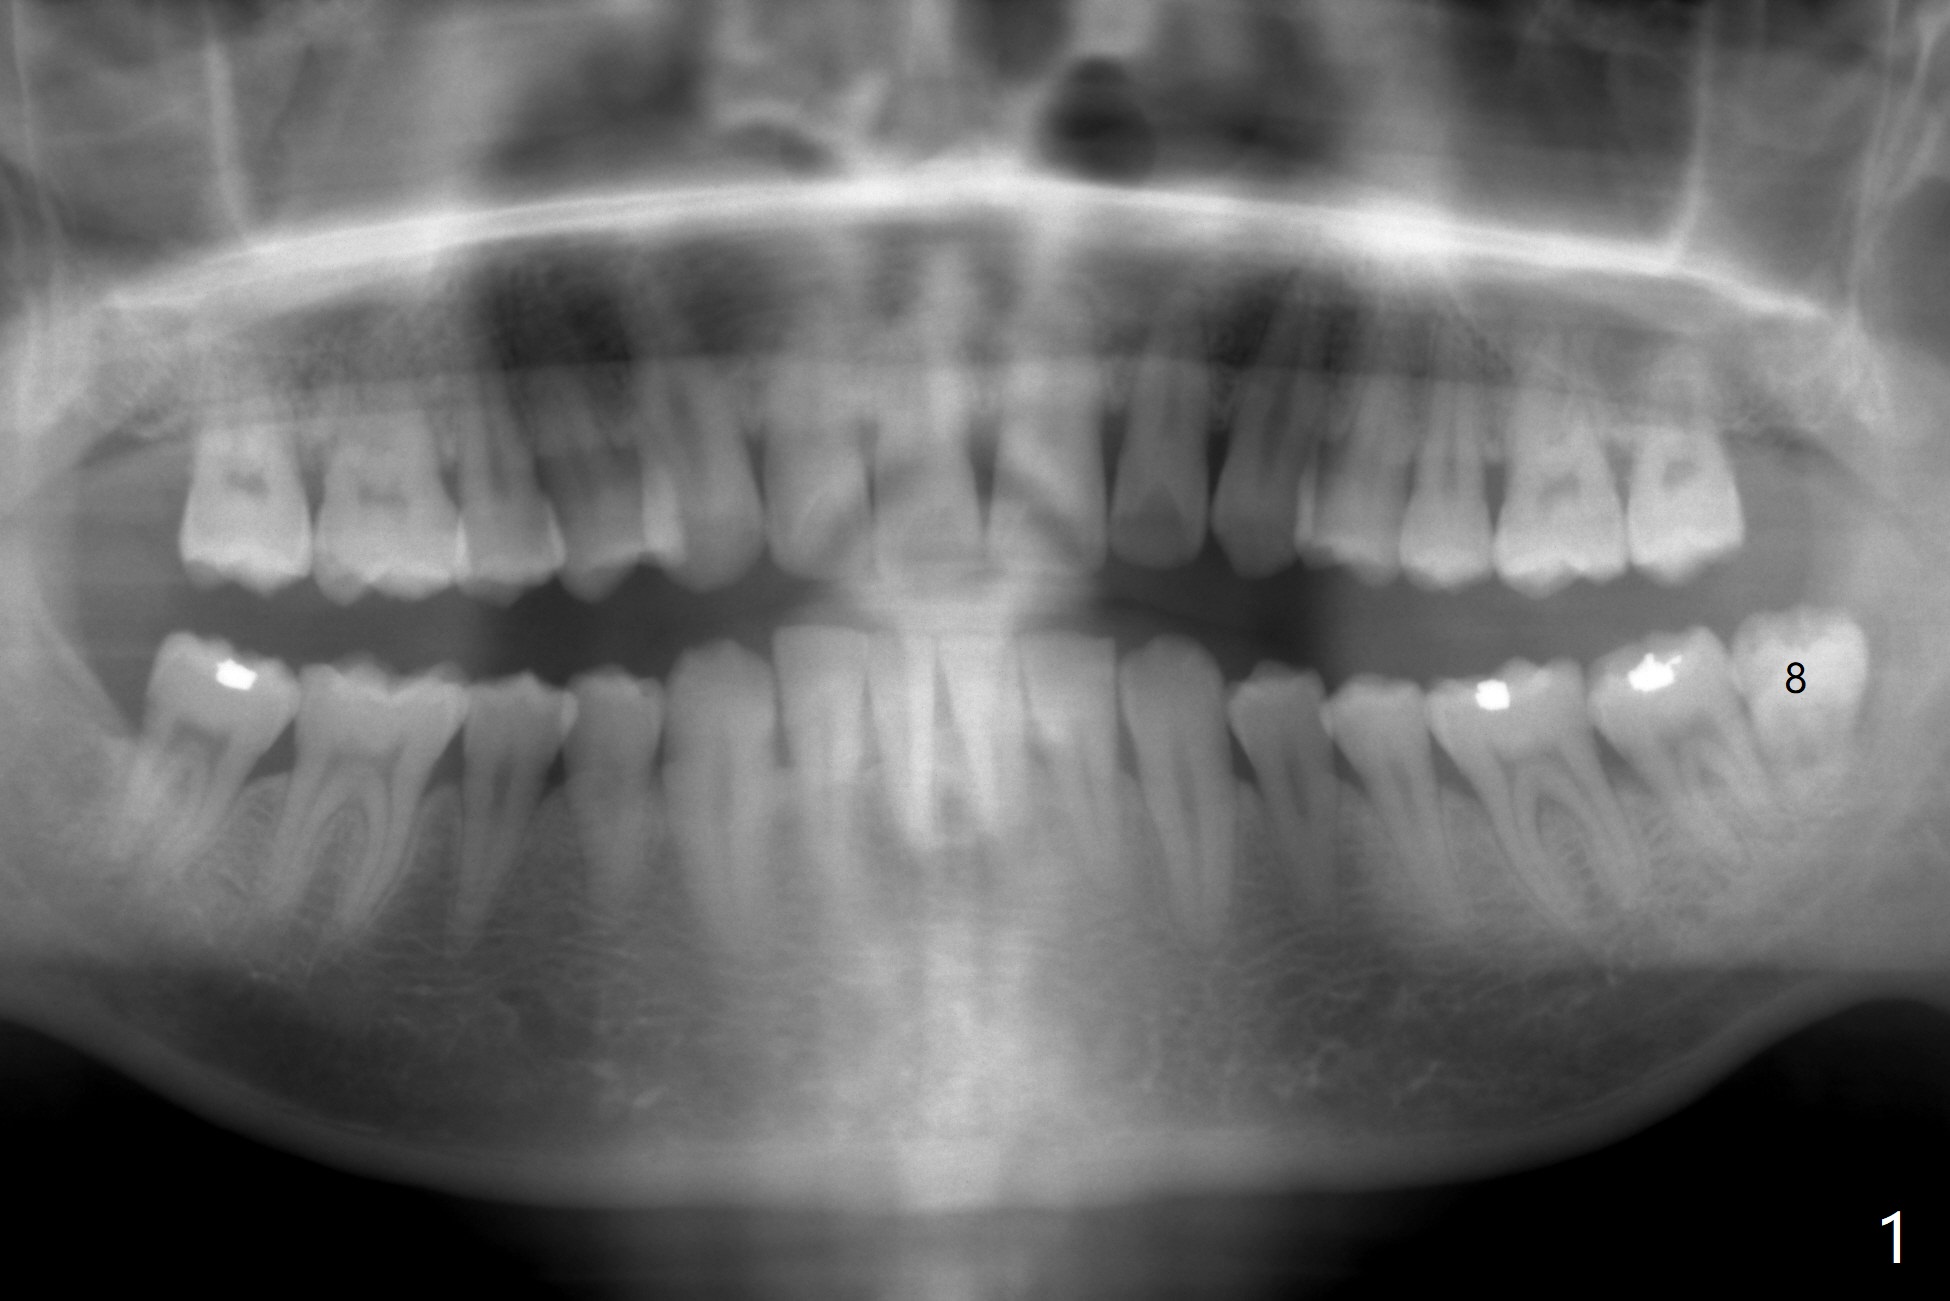

第二第三磨牙之间无骨

55岁男13年前就诊深洗同时拔除左下智齿(第二第三磨牙之间无骨,图一),拔除后没有植骨。十年后第二磨牙远中出现骨缺损(图二),十三年后第二磨牙松动(图三),需要拔除种植(图四)。其实当年拔除后必须植骨(图一’:红色 (白色:膜或者塞)),甚至种植(图一”:绿色),植骨。Thirteen years post #17 extraction, the lingual plate (L) is lower than the buccal one (B). Return to Prevent Molar Periimplantitis (Protocols, Table) No Caries No Antibiotic Plug 提升 手术 Xin Wei, DDS, PhD, MS 1st edition 03/27/2021, last revision 05/31/2021